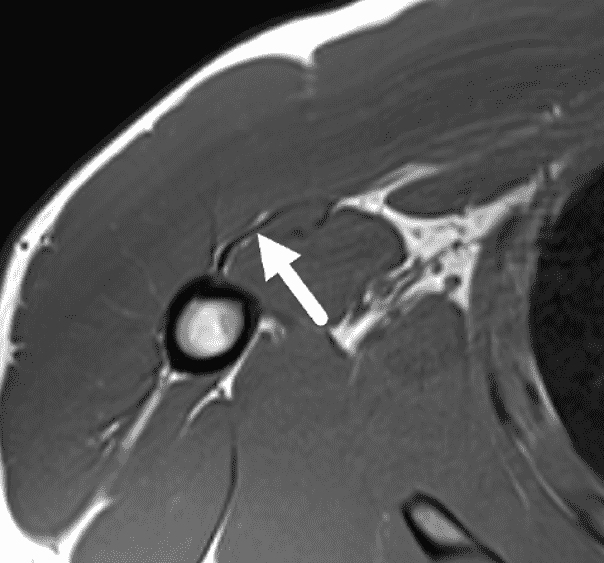

Secondary signs include hematoma, edema contacting the anterior humeral surface and anterior displacement of the long head of biceps tendon (LHBT) due to loss of the overlying retinacular function of the torn PM tendon (Figure 8A).15,19 In a series of 26 subjects, Godoy et al. found LHBT displacement of 4.5 mm or greater from the floor of the bicipital groove provided 86% sensitivity and 75% specificity for complete, 2-layer PM tendon tears from the humeral attachment.15 Baker et al, found edema contacting the anterior margin of the humerus helped improve radiologist’s ability to accurately distinguish tendon avulsions from MT injuries in the acute or subacute setting.19 Occasionally, if a PM injuries is unsuspected clinically, a shoulder joint MRI may be requested rather than a chest wall examination. Subtle findings suggesting a PM injury may be visible on shoulder images. The “smoke sign” was recently proposed to help identify PM injuries – especially humeral avulsions – in this scenario.20 The appearance of smoke billowing from a distant horizon is created by edema lateral (on coronal images) and anterior (on sagittal and axial images) to the short head biceps and coracobrachialis, with a relatively sharp margin (Figure 11). The sharp demarcation provided by these tendons constitutes the horizon of the smoke sign. The sign is not intended to be used as a method of distinguishing between humeral attachment and MT injuries. Of the group of 38 test subjects, the smoke sign was present in 24/24 humeral avulsions, 4/4 intratendinous injuries, 4/8 MT injuries and 0/2 intramuscular injuries.20

Figure 11: “Smoke sign” as a clue to a pectoralis major injury on shoulder MRI. (11A) Axial T2-weighted image from a shoulder MRI does not extend distally to include the pectoralis major tendon but shows edema along the anterior margin of the coracobrachialis muscle (arrows), the “smoke sign.” (11B) Sagittal T2-weighted image from a shoulder MRI shows a sharp posterior margin of the edema along the muscles (arrows). CB/B = coracobrachialis/short head biceps muscle bellies. (11C) Because of the findings on the shoulder images, the patient returned two days later for a dedicated chest wall MRI, with a fat-suppressed axial T2-weighted image from that study confirming a completely torn, retracted pectoralis major tendon (arrow).